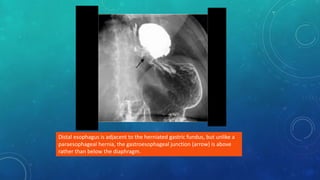

Distal esophagus is adjacent to the herniated gastric fundus, but unlike a

paraesophageal hernia, the gastroesophageal junction (arrow) is above

rather than below the diaphragm.